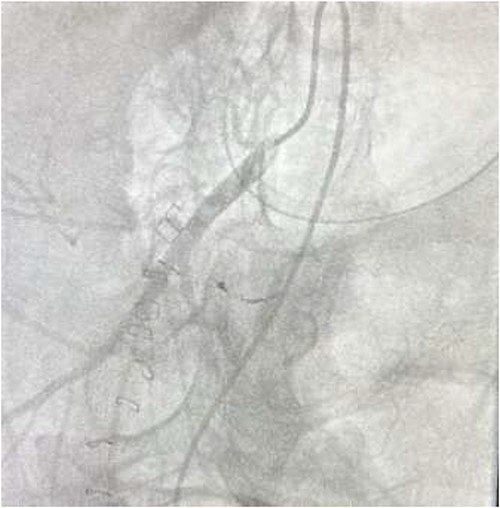

The on-call interventional radiology team performed a successful embolization. A 6-French Sheath was passed through the left common femoral artery, and a 5-French Sim-1 catheter was advanced into the coeliac and common hepatic artery. A 2.4 French Direxon microcatheter was advanced into a branch of the superior mesenteric artery at the site of bleeding. Successful coil embolization with a 2 mm × 2 mm concerto micro coil was performed. A satisfactory angiographic result with DYNA-CT, also known as modern C-arm CT or cone-beam CTA, showed no extravasation.

There were no immediate complications to the procedure. The patient returned to intensive care post-operatively. He remained intubated and vital laboratory tests were stabilized. He experienced acute renal failure post-procedure that required haemodialysis and prolonged intubation (Figs 3 and 4).